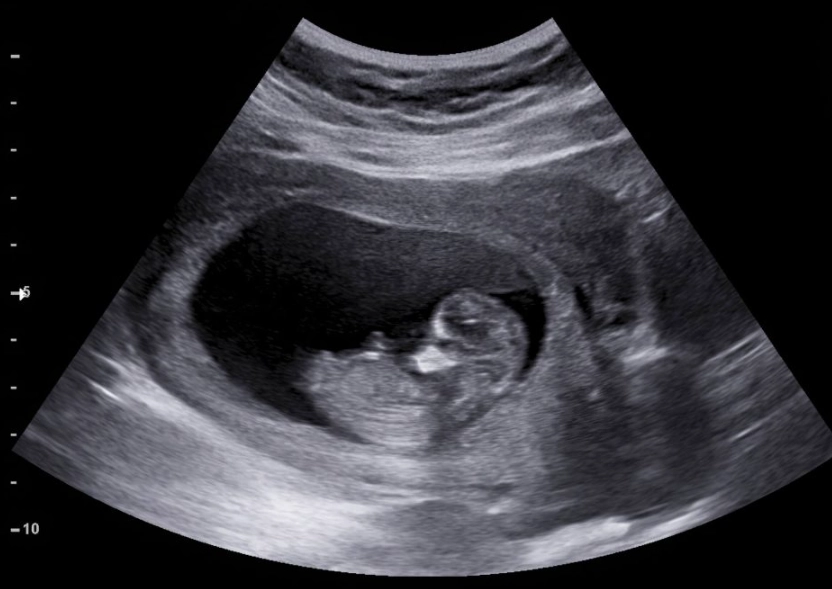

This is where a lot of anxiety lives. The tech might be quiet, the images might look like blurry space photos to you. Let's decode some common scenarios after a pregnancy 1 month ultrasound.

This is incredibly common at 4-5 weeks. The report might say something like "gestational sac visualized, fetal pole not yet identified." This doesn't automatically mean something is wrong. It often just means it's too early. Your doctor will likely recommend a follow-up ultrasound in 1-2 weeks. During that time, the embryo should grow enough to become visible. The wait is tough, but it's a standard part of early pregnancy management.

The "Everything Looks On Track" Scenario

If they see a gestational sac in the uterus that measures appropriately for your dates, that's a great first sign. It confirms an intrauterine pregnancy, which is a major relief. They'll give you an estimated due date based on the sac size and schedule your next prenatal appointment or scan for a few weeks later.